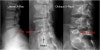

X-ray : 척추분리증(Spondylolysis)